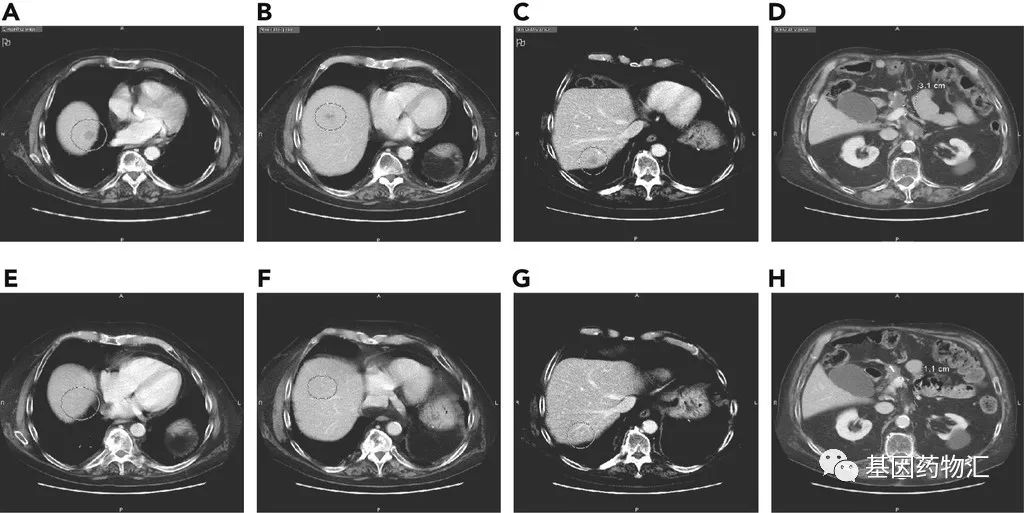

Sotorasib对于一部分存在多发转移的患者,同样有非常好的疗效。举例来说,一位64岁的女性患者,基线时存在肝脏、淋巴结、肺以及腹膜多个部位的转移,之前曾经接受过FOLFIRINOX方案的治疗。在接受Sotorasib治疗之前,她的肝脏上有一个直径2.2厘米的病灶;治疗18周后,病灶缩小到了0.8厘米。